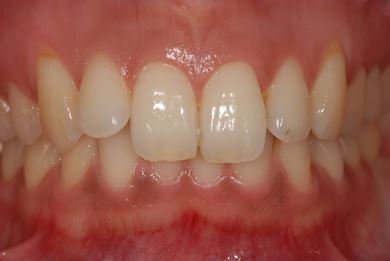

| 性別/年齢 | 女性 / 30歳 | ||||||||||||||||||||||||||||||||

| 主訴 | 銀歯がはずれた奥歯にひびが入っており、抜歯しなければいけないため、インプラントの治療相談を希望。 | ||||||||||||||||||||||||||||||||

| 治療内容 | インプラント1本、メタルボンドセラミック1本 | ||||||||||||||||||||||||||||||||

| 総治療費 | 401,363円 | ||||||||||||||||||||||||||||||||

| 治療期間 | 5ヶ月 |